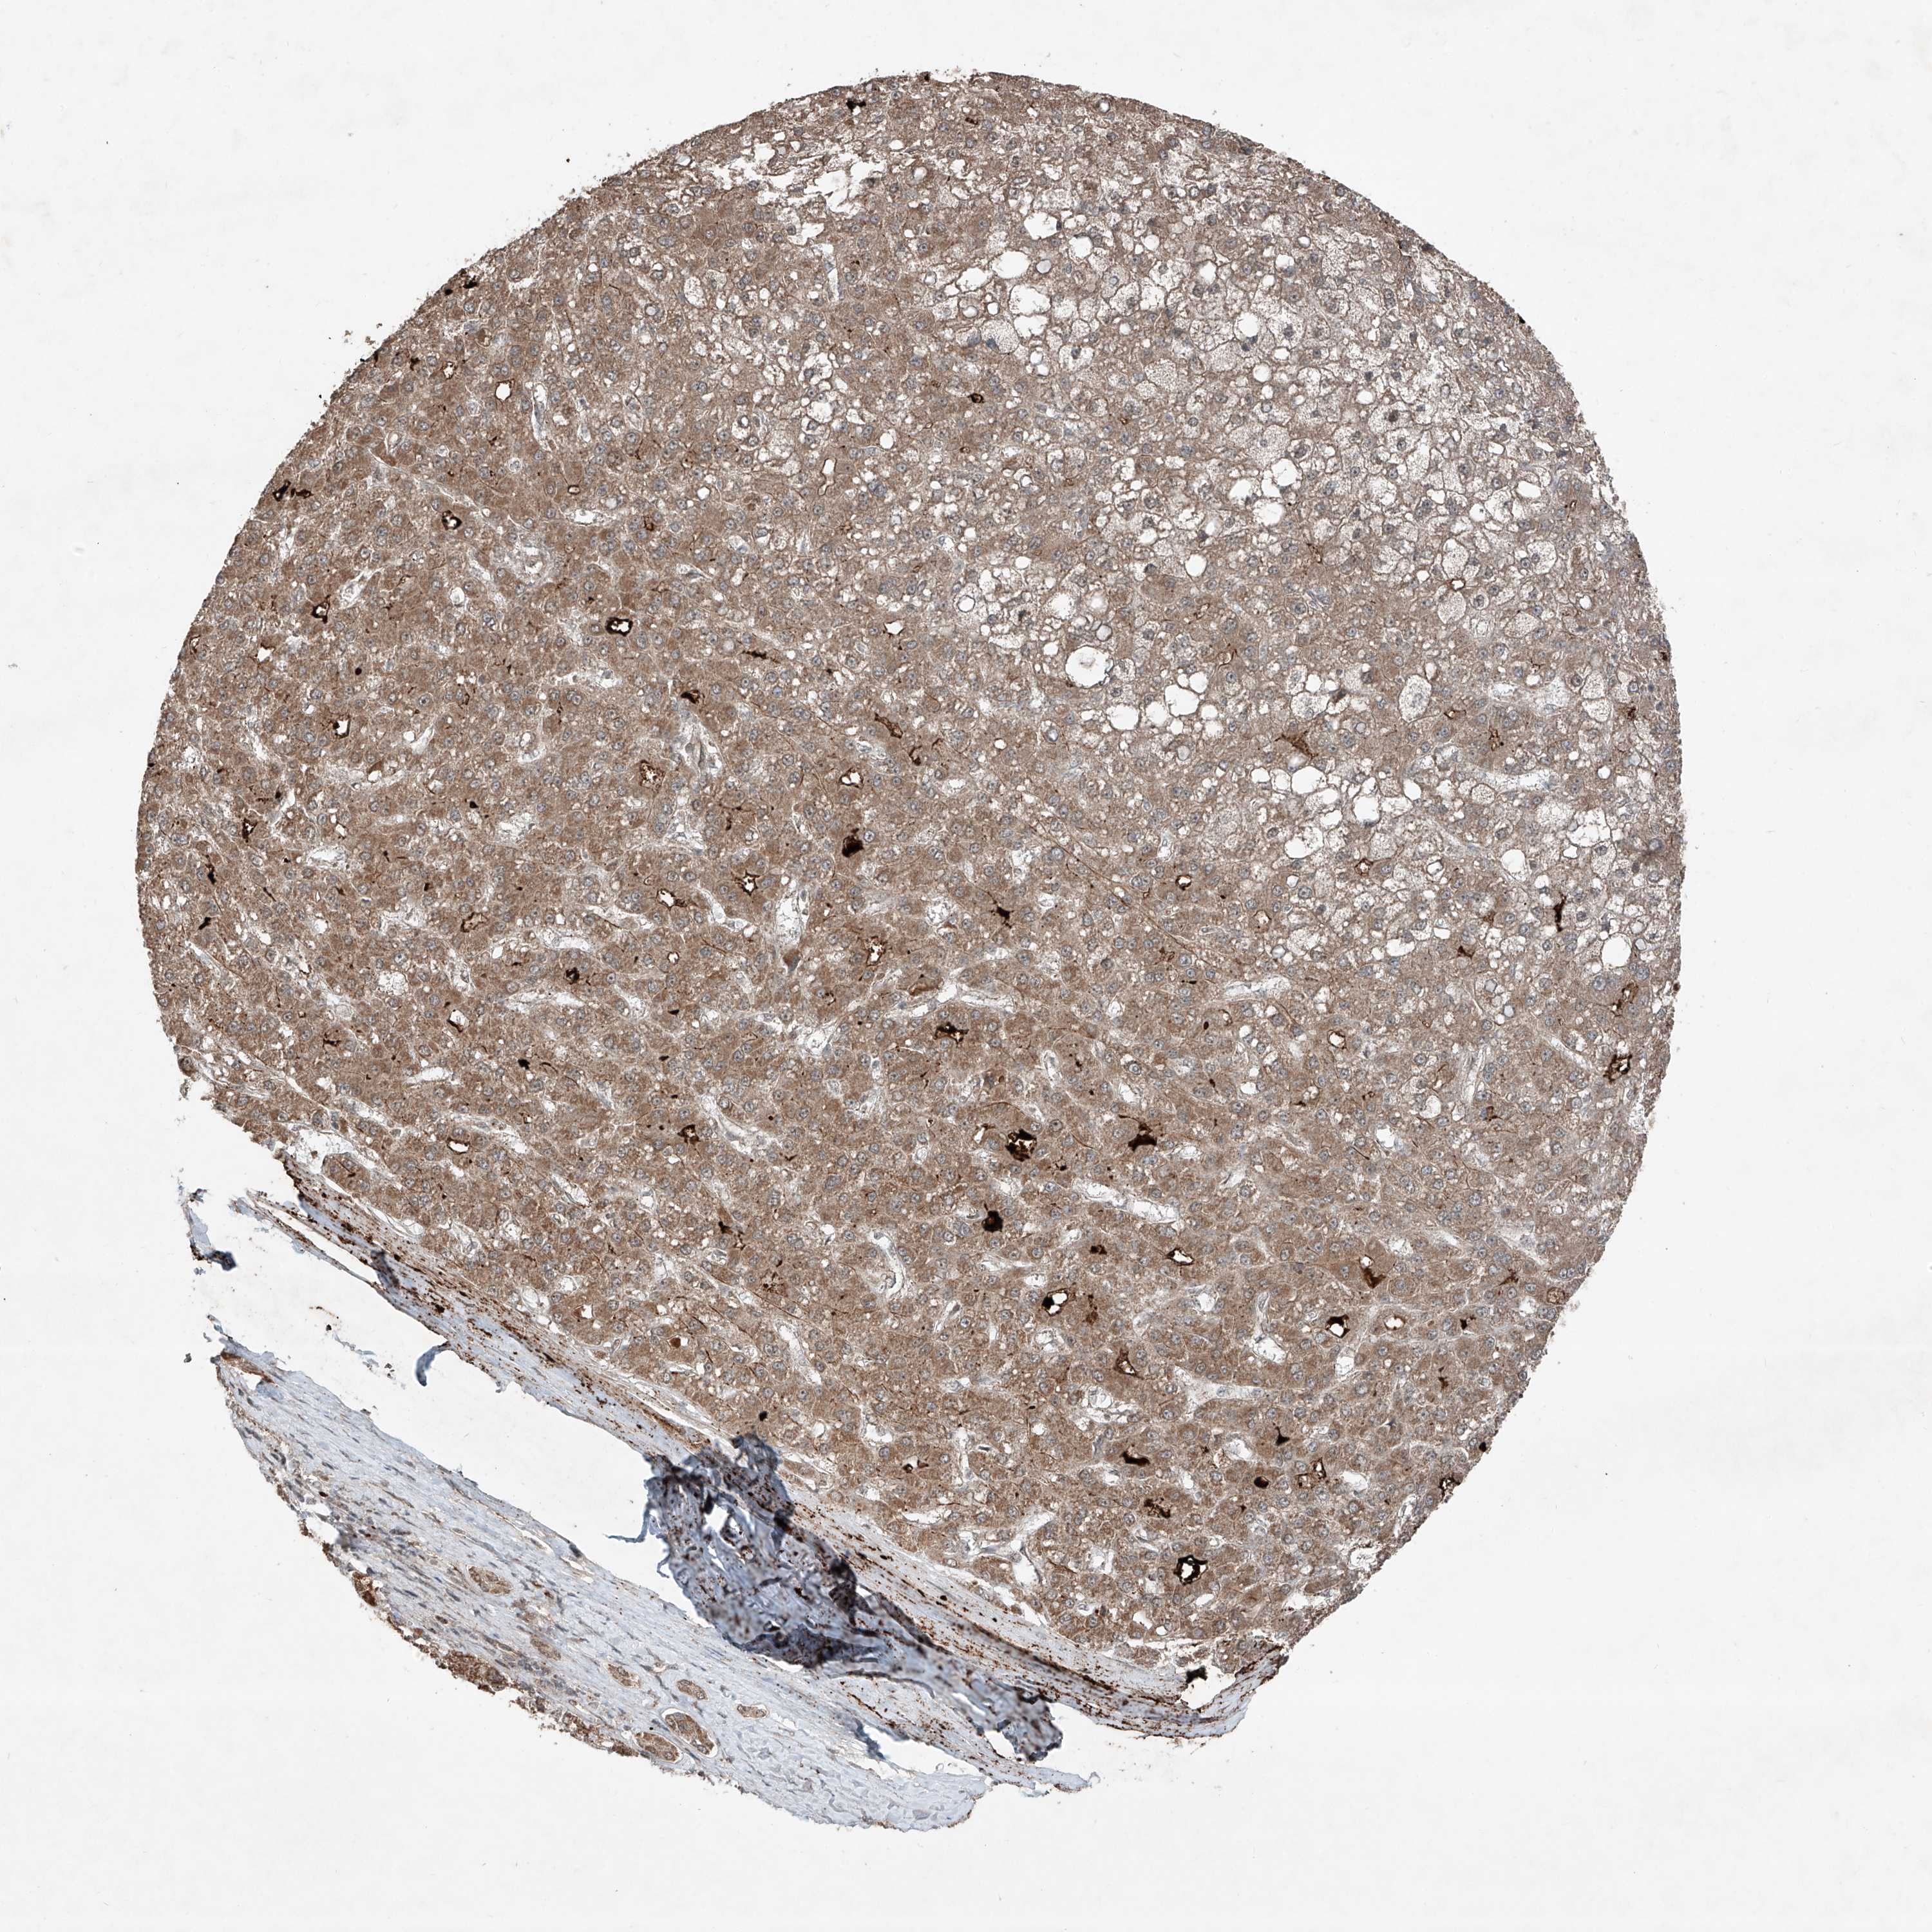

LIVER CANCER - Protein expressioni

A mouse-over function shows sample information and annotation data. Click on an image to view it in a full screen mode. Samples can be filtered based on level of antibody staining by selecting one or several of the following categories: high, medium, low and not detected. The assay and annotation is described here.

Note that samples used for immunohistochemistry by the Human Protein Atlas do not correspond to samples in the TCGA dataset.

Antibody stainingi

Antibody staining in the annotated cell types in the current human tissue is reported as not detected, low, medium, or high, based on conventional immunohistochemistry profiling in selected tissues. This score is based on the combination of the staining intensity and fraction of stained cells.

Each image is clickable and will lead to virtual microscopy that enables deeper exploration of all samples and also displays staining intensity scores, fraction scores and subcellular localization as well as patient and tissue information for each sample.

Antibody HPA031452

Staining

High

Medium

Low

Not detected

Intensity

Strong

Moderate

Weak

Negative

Quantity

>75%

75%-25%

<25%

None

Location

Nuclear

Cytoplasmic/membranous

Cytoplasmic/membranous,nuclear

Cholangiocarcinoma

Carcinoma, Hepatocellular, NOS